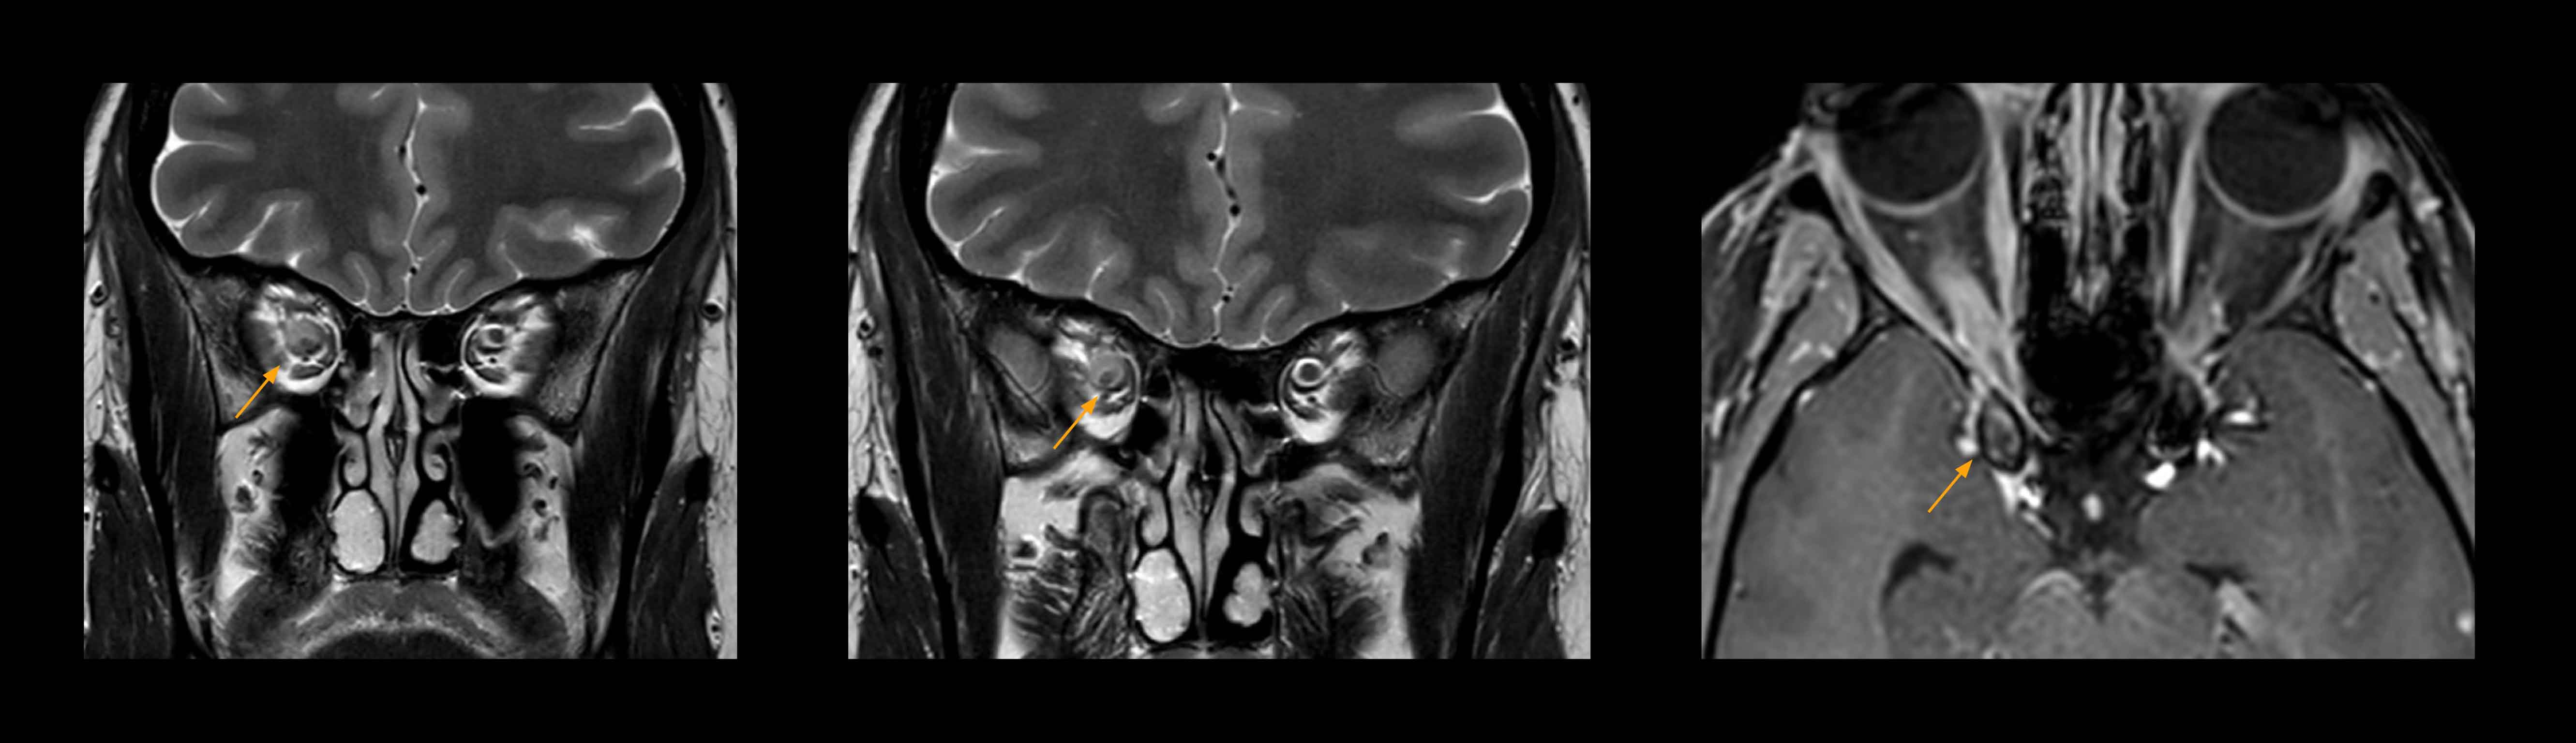

Imaging of the optic nerve sheath

High-resolution MRI impressively demonstrates the compression and narrowing of the right optic nerve in this case of optic nerve sheath meningioma (ONSM). The coronal T2-weighted images show the hyper-intense, half-moon shaped lesion, that is clearly visible in the axial T1W image after contrast injection (right). These imaging findings were so convincing that there sponsible neurosurgeon did not consider a pretherapeutic histological clarification.

High resolution-MRI impressively demonstrates the compression and narrowing of the right optic nerve in this case of optic nerve sheath meningioma (ONSM). The coronal T2-weighted images show the hyper-intense, half-moon shaped lesion, that is clearly visible in the axial T1W image after contrast injection (right). These imaging findings were so convincing that there sponsible neurosurgeon did not consider a pretherapeutic histological clarification.

High resolution providing diagnostic confidence

In select cases, the MR 7700 has helped the hospital’s physicians more clearly visualize pathology. “We’re definitely getting the impression that tumors are better delineated with the MR7700,” Dr. Heindel says. “For example, I examined a patient who had been diagnosed in another hospital with possible neuritis of the optic nerve. However, the MR 7700 images allowed me to diagnose it as an optic nerve sheath meningioma, a rare and often misdiagnosed, slowly growing tumor that wascausing the visual disturbances in the patient. The lesion was so well delineated on the high resolution MR 7700 images that our neurosurgeon decided he did not need a biopsy before proceeding directly with decompression of the optic canal and peeling away those tumor cells.”